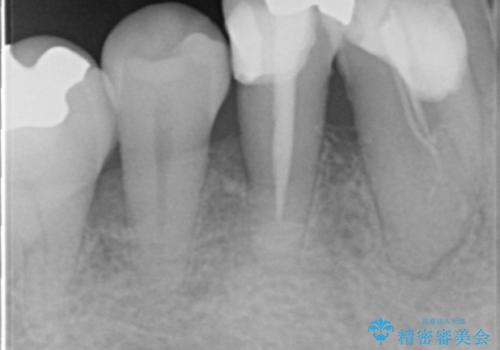

- 全顎的な重度歯周病の患者様です。

骨吸収の進行している右下臼歯部に、再生療法(骨を増やす手術))を行いました。

再生療法から1年後、リエントリー手術により骨の再生を確認し、骨外科処置(骨を平らにして歯周ポケットの根本的な改善を図る処置)を行いました。